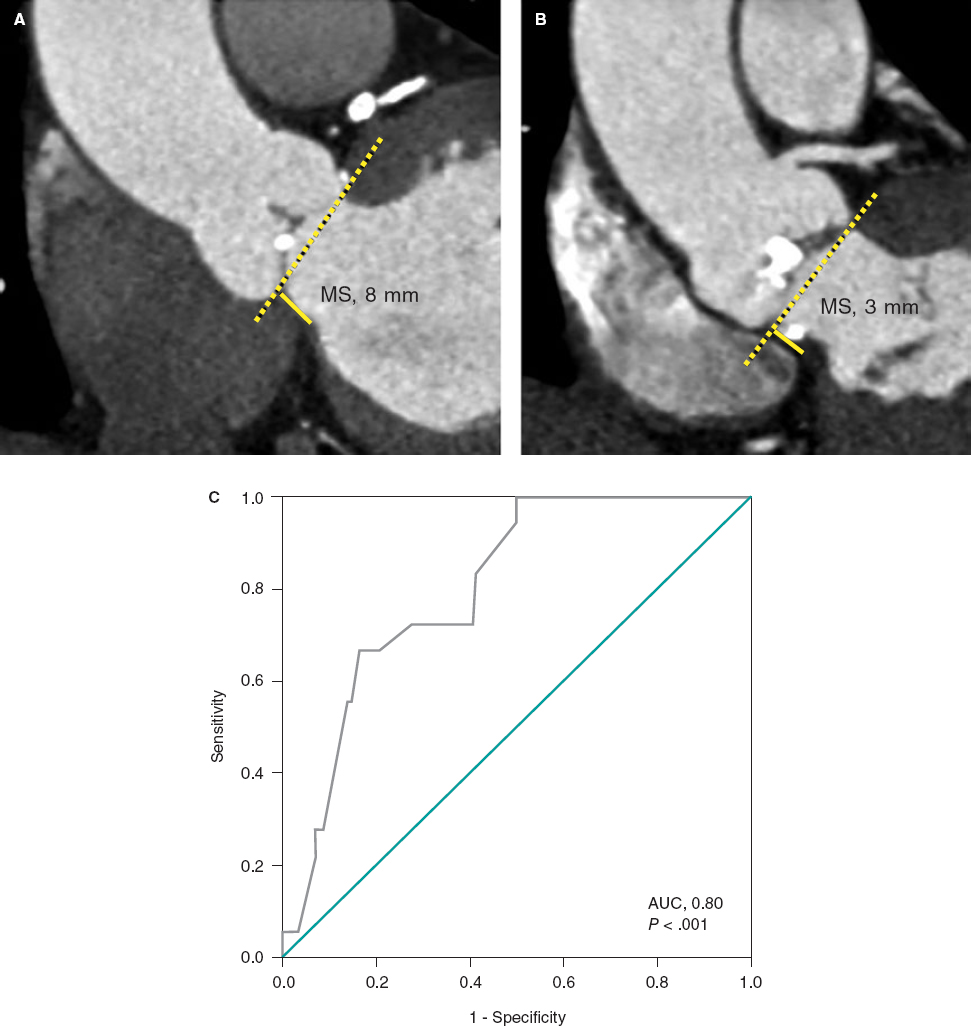

The mitral valve showed a thickened posterior leaflet without damage to the anterior one. Microscopically, the posterior leaflet showed focal thickening with increased deposition of mucopolysaccharides and vascularization of the proximal part with distal reduction in the number of vessels. The infarction regions were histologically characterized by the presence of mature connective tissue including islets of cardiac muscle fibers and inflammatory cells.

In the macroscopic examination, the mitral valve showed thickened leaflets with hemorrhages in their atrial surface (figure 1A of the supplementary data). Histologically and added to the already mentioned hemorrhages, both leaflets appeared thickened due to the deposition of mucopolysaccharides, especially in the middle layer (figure 1B,C of the supplementary data). Small caliber vessels were seen together with a mild inflammatory response figure 2 of the supplementary data. The infarction regions were characterized by the presence of mature connective tissue including islets of cardiac muscle fibers with similar characteristics compared to animal #1.